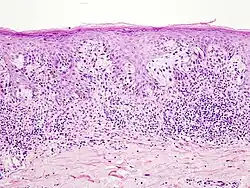

Superfiziell spreitendes Melanom

Das superfiziell spreitende Melanom entsteht in bedeckter, üblicherweise nicht dem Sonnenlicht ausgesetzter Haut. Vorausgegangene Sonnenbrände in der Kindheit und wiederholte Sonnenlichteinstrahlung im Erwachsenenalter sind dennoch ursächlich bedeutsam. Der Tumor wächst überwiegend horizontal zunächst als auf die Epidermis beschränktes Melanoma in situ. Die epidermale Komponente ist zumeist breit und unscharf begrenzt, aber auch scharf begrenzte Läsionen bei klinisch unregelmäßiger Kontur kommen vor.

Die Melanozyten haben große Zellkerne, die häufig auch vergrößerte Nukleolen aufweisen. Mitosen sind in der epidermalen Komponente selten. Das Zytoplasma ist üblicherweise weit und der Pigmentgehalt kann innerhalb einer Läsion stark wechseln. Die Tumorzellen breiten sich einzeln oder in unregelmäßigen, teils miteinander verbundenen Nestern in der Epidermis aus und folgen dabei Adnexstrukturen. Typisch für das superfiziell spreitende Melanom ist das als pagetoid bezeichnete Wachstumsmuster: atypische Melanozyten finden sich nicht nur entlang der Junktionszone, sondern verteilt über die ganze Breite der Epidermis bis in oberflächliche Zelllagen.

Die dermale Komponente superfiziell spreitender Melanome ist in der Regel asymmetrisch aufgebaut. Eine Ausreifung der Melanozyten fehlt und es finden sich Mitosen. Selten zeigen sich nekrotische (abgestorbene) Melanozyten. An der Basis des Tumors und eventuell auch zwischen den Tumorzellen besteht ein hauptsächlich lymphozytäres Entzündungsinfiltrat.[44]

- Superfiziell spreitendes Melanom

-

Unregelmäßige melanozytäre Nester, hier überwiegend entlang der Junktionszone. -

Einzelmelanozyten und unregelmäßige melanozytäre Nester auch in mittleren Schichten der Epidermis